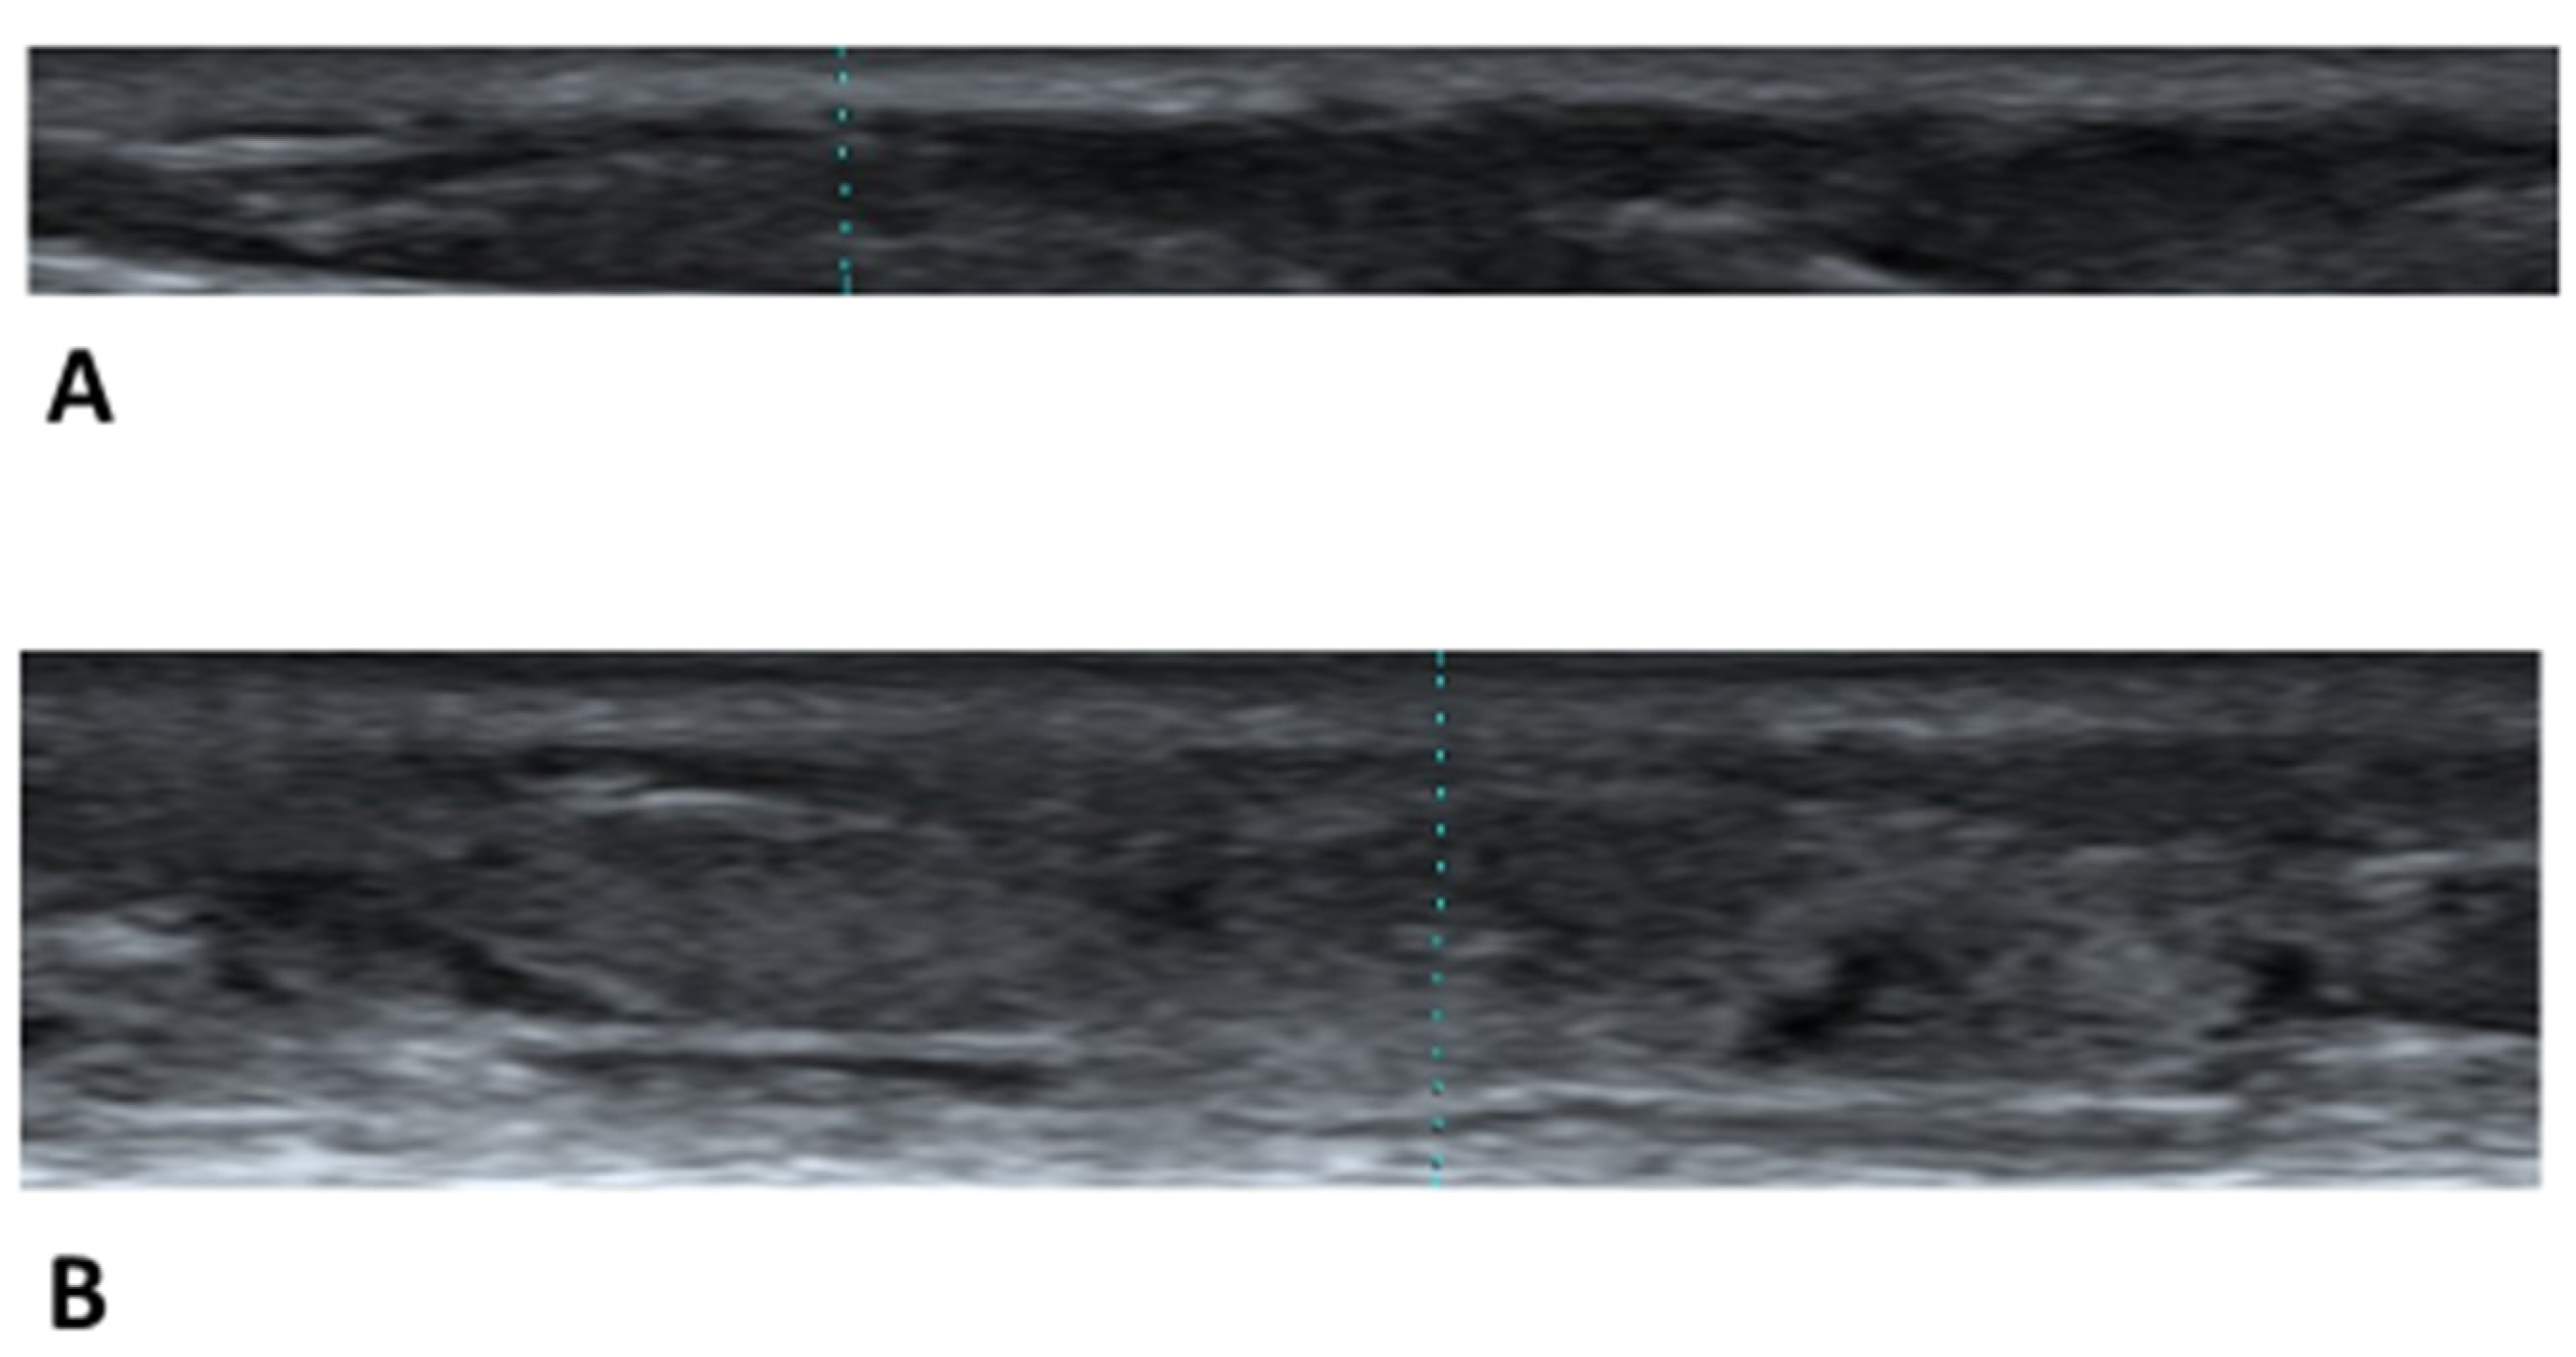

2.2. Ultrasound Images of the Skin with Leg Edema